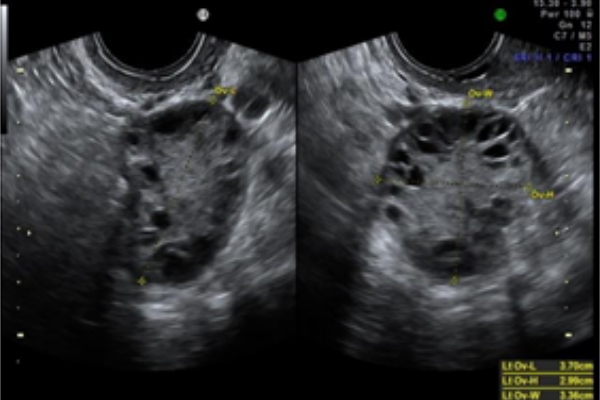

SINDROME DE OVARIOS POLIQUÍSTICOS

Es un trastorno endocrino y metabólico, que condiciona un desequilibrio en las hormonas sexuales femeninas. Puede afectar al 6-10% de las mujeres en edad fértil, en especial entre los 20 y 30 años. No existe un test único para su diagnóstico. Sino, que existe un...